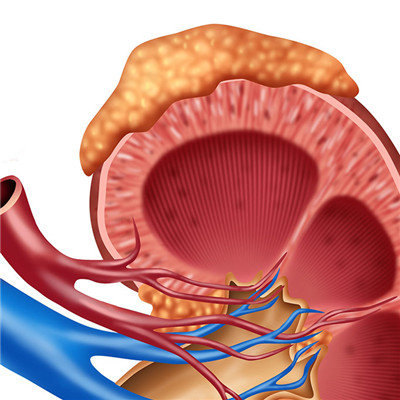

Got nephritis serious? This is what many patients are thinking. Some patients don't even know that they will get this disease. In fact, different patients with nephritis have different manifestations. Some patients will have edema, low back pain and weakness. Some patients have nephritis without any obvious reaction. It's not easy to find it. No matter what symptoms, if they get nephritis and don't treat it for a long time, It may eventually lead to uremia. So for patients with nephritis, if found their own condition, must be treated as soon as possible.

In addition, patients with chronic nephritis often appear edema, which can be used as a standard for the diagnosis of this disease. When you get up in the morning, you will see swelling around your eyes and face, and serious edema will appear all over the body. So found that he appeared edema, must go to the hospital for examination, just in case

Medical experts have reminded that we must attach great importance to nephritis. Once diagnosed with nephritis, early treatment is the most critical. Patients with nephritis often have hypertension. For patients with chronic nephritis, hypertension will occur sooner or later, which may be persistent or intermittent.

For many patients with nephritis, if you can early detection, and take the correct treatment measures, it can avoid the occurrence of uremia, at the same time for patients with nephritis, a good living habits is very important, and find yourself sick after not nervous, as soon as possible to take the right treatment is the first priority.